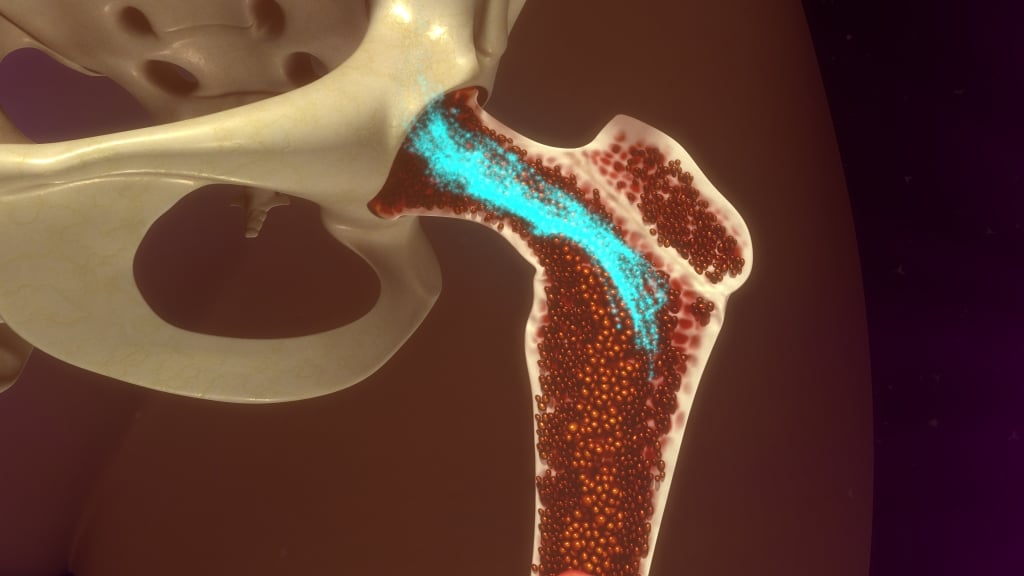

La campagna, lanciata dal Ministero della Salute e dal Centro Nazionale Trapianti, punta a sensibilizzare le nuove generazioni sulla donazione degli organi. L’attività è in crescita, ma sono ancora novemila le persone in lista di attesa Iniziative nelle piazze italiane fino a domenica per ampliare il registro dei donatori. La procedura viene adottata per curare leucemie, linfomi, mielomi, anemie gravi e immunodeficienze

Iniziative nelle piazze italiane fino a domenica per ampliare il registro dei donatori. La procedura viene adottata per curare leucemie, linfomi, mielomi, anemie gravi e immunodeficienze E’ solo in caso di morte cerebrale, attentamente valutata da una commissione, che avviene il prelievo per un trapianto d'organo. Coma e stato vegetativo non c'entrano con la donazione di organi